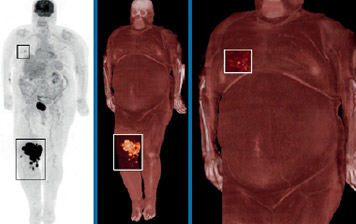

Time-of-Flight-Rekonstruktion anhand von SSS mit Tail-Fitting (jeweils linkes Bild des Bildpaars) und ×Clean (jeweils rechtes Bild). Die Artefakte, die bei der SSS mit Tail-Fitting auftreten, treten bei den ×Clean-Rekonstruktionen nicht auf.

Bild mit freundlicher Genehmigung der University of Pennsylvania School of Medicine, Philadelphia, USA

Die Streustrahlenkorrektur ist für eine hohe Bildqualität unerlässlich. Es können jedoch photopenische Artefakte auftreten, wenn das Ergebnis der Simulation der Einfachstreuung (Single Scatter Simulation, SSS) anhand von klassischem Tail-Fitting skaliert wird, insbesondere bei adipösen Patienten oder bei Bewegungen des Patienten.

×Clean ist eine hybride Methode zur Streustrahlenkorrektur bei der Rekonstruktion von PET-Bildern. Dank dieser Methode liefert das Ingenuity TF PET/CT eine bessere Bildqualität mit reduzierten Artefakten. ×Clean ist eine robustere Methode zur Streustrahlenkorrektur als SSS mit Tail-Fitting. Die Ergebnisse der SSS-Modellierung werden dabei anhand eines Ableitungsfaktors aus einer Monte-Carlo-Simulation – einer rechenintensiveren Modellierungsform – skaliert.